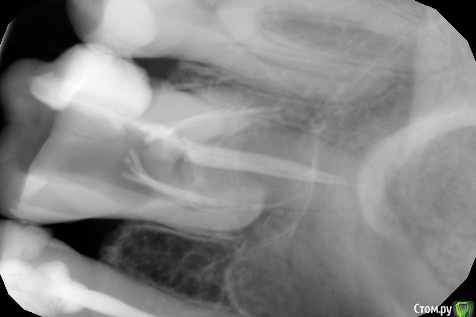

ЛолаN Опубликовано 29 мая, 2018 Поделиться Опубликовано 29 мая, 2018 Добрый день.2 недели назад стал беспокоить зуб.На осмотре стоматолог предложил его удалить. Так как удалять не хотелось, решено было лечить. Доктору добраться удалось только до одного канала.В итоге его рассверлили, почистили и отправили гулять 2 недели. 2 дня назад зуб стал снова беспокоить.После полоскания с содой стала выходить зеленоватая жидкость и зуб перестал беспокоить. Вчера был сделан снимок. Скажите, подлежит ли лечению и восстановлению зуб? Ссылка на комментарий

red_butler Опубликовано 29 мая, 2018 Поделиться Опубликовано 29 мая, 2018 Спасибо за ответ.Не могли бы вы пояснить, почему невозможно восстановить?Большая степень разрушения Ссылка на комментарий